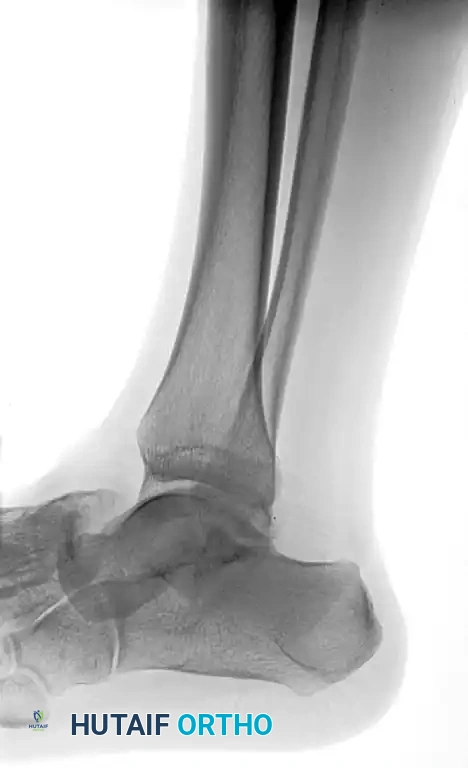

Standard trauma radiographs of the ankle (AP, lateral, and mortise) and foot (AP, lateral, and oblique) are required.

Radiographic appearance of a medial subtalar dislocation. The talonavicular and talocalcaneal joints are completely disrupted.

Radiographs demonstrating a lateral subtalar dislocation before and after reduction.

After closed reduction of the dislocation, no fracture is apparent on the standard lateral radiograph.

Radiographic appearance after open reduction and internal fixation of the identified talar fracture.